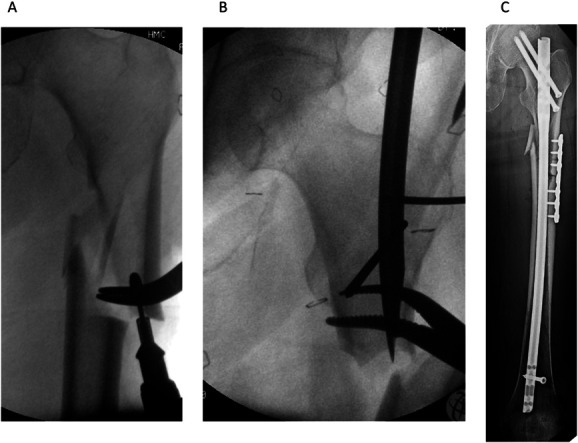

Geriatric trauma continues to rise, corresponding with the continuing growth of the older population. These fractures continue to expand, demonstrated by the incidence of hip fractures having grown to 1.5 million adults worldwide per year. This patient population and their associated fracture patterns present unique challenges to the surgeon, as well as having a profound economic impact on the health care system. Pharmacologic treatment has focused on prevention, with aging adults having impaired fracture healing in addition to diminished bone mineral density. Intraoperatively, novel ideas to assess fracture reduction to facilitate decreased fracture collapse have recently been explored. Postoperatively, pharmacologic avenues have focused on future fracture prevention, while shared care models between geriatrics and orthopaedics have shown promise regarding decreasing mortality and length of stay. As geriatric trauma continues to grow, it is imperative that we look to optimize all phases of care, from preoperative to postoperative.